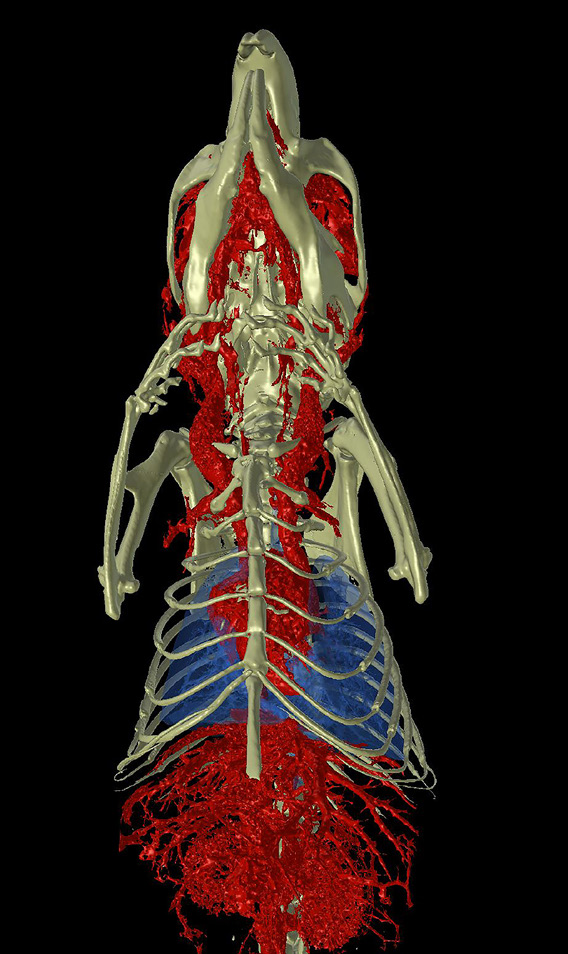

GX IIIは、マウスから小型ウサギまでのさまざまな種のin vivoイメージングだけでなく、より高解像度なex vivo イメージングも可能となり、さまざまなサンプルをより最適な測定方法で撮影できる幅広い柔軟性を提供します。

- 5種のFOV:8mm, 18mm, 36mm, 72mm, 86mm

マウス・ラット・フェレット対応

2相心拍・呼吸同期CT

心拍や呼吸による動きは、CT画像のアーティファクトの原因となります。GX IIIは画像ベースの同期技術により、マウス、ラット、フェレットの心臓・肺イメージングを高精度に実現します。

撮影後、心臓や横隔膜に設定したROIをもとに独自アルゴリズムで同期処理を行い、アーティファクトを低減。心拍・呼吸周期の特定フェーズのデータを再構成することで、画質と定量精度を向上させます。

心臓・肺のin vivoイメージングなど、動きの影響を受けやすい研究に最適です。